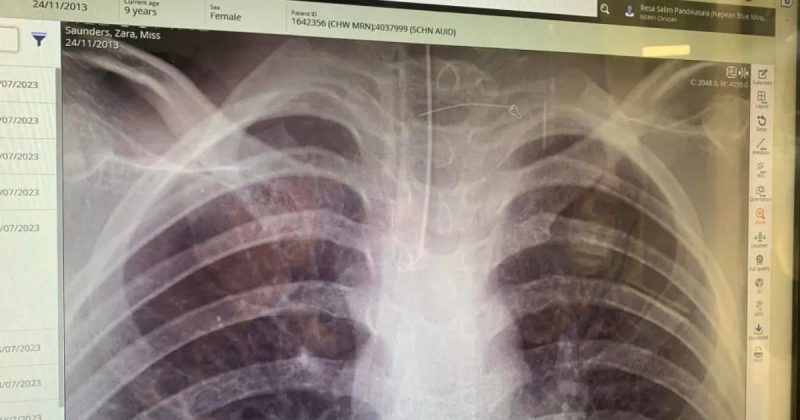

Segundo o New York Post, a cerda perfurou o esôfago e penetrou na artéria carótida da menina, causando uma grave infecção e danos neurológicos.

Mais tarde, o diagnóstico foi revelado: um abscesso cerebral. Durante uma tomografia de urgência, os médicos encontraram o objeto responsável pela confusão. Parecida com um fio de cabelo, a cerda estava no pescoço da menina.